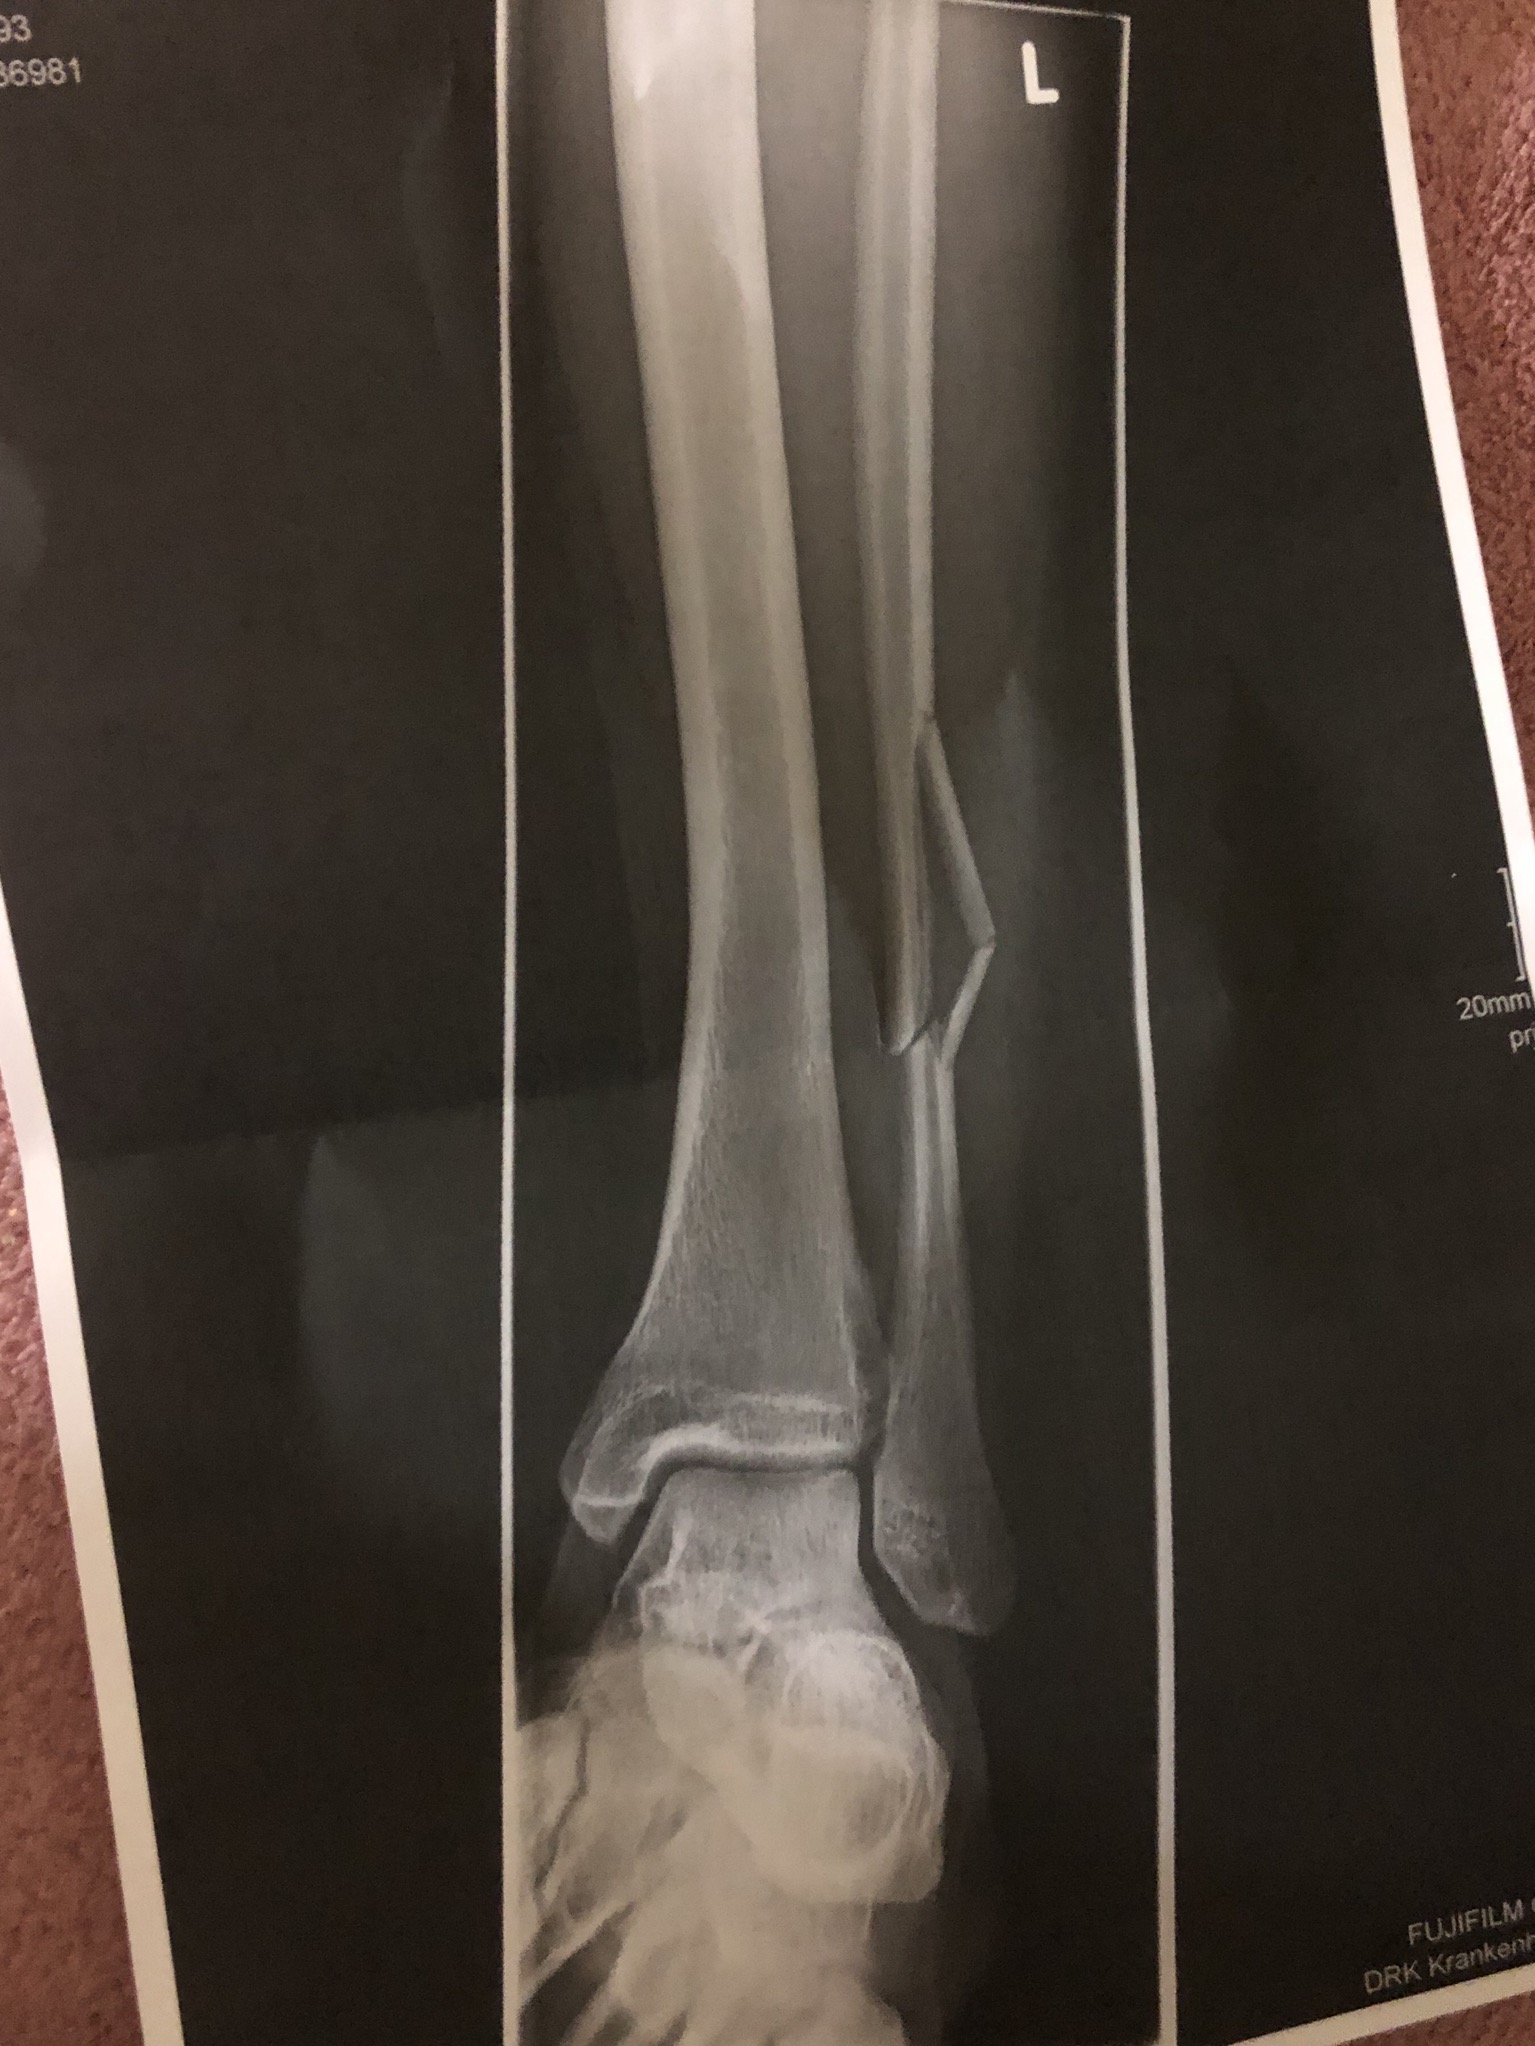

Die Bewegungen sind meist eingeschränkt, eine Belastung des .Bruch im unteren Teil des Schienbeins, der den Innenknöchel am Sprunggelenk bildet (distale Tibiafraktur, Pilon-tibiale-Fraktur).

Dies ist eine ernsthaftere Verletzung, bei der ein oder mehrere Knochen des Sprunggelenks betroffen sein können. Als erste Maßnahme bei einem Wadenbeinbruch muss der Patient das .Auch eine Verletzung der Syndesmose (dem Band zwischen Tibia und Fibula) kann eine Ursache für Schmerzen und Schwellungen am Wadenbein sein. Eine der häufigsten Ursachen für Wasseransammlungen in den Beinen ist eine schlechte Durchblutung, die dazu führt, dass das Blut nicht richtig .

Also lass uns anfangen! Wasser kann in den Beinen auf verschiedene Arten auftreten. Orthopäden wollten auch keine KG verschreiben, .Die Fibula ( Wadenbein) ist einer der beiden Knochen des Unterschenkels. Fraktur des Schienbeinkopfes. Zusammen mit dem Schienbein (Tibia), an das es sich auf der Außenseite anlegt, bildet es den menschlichen Unterschenkel. Bei der Tibiakopffraktur bricht das Schienbein im Kniegelenk.Wadenbeinköpfchen (caput fibulae) Der Kopf hat eine Spitze (apex capitis fibulae) Wadenbeinköpfchenspitze (apex capitis fibulae) und eine Gelenkfläche (facies articularis capitis fibulae), die mit dem Schienbein verbunden ist.